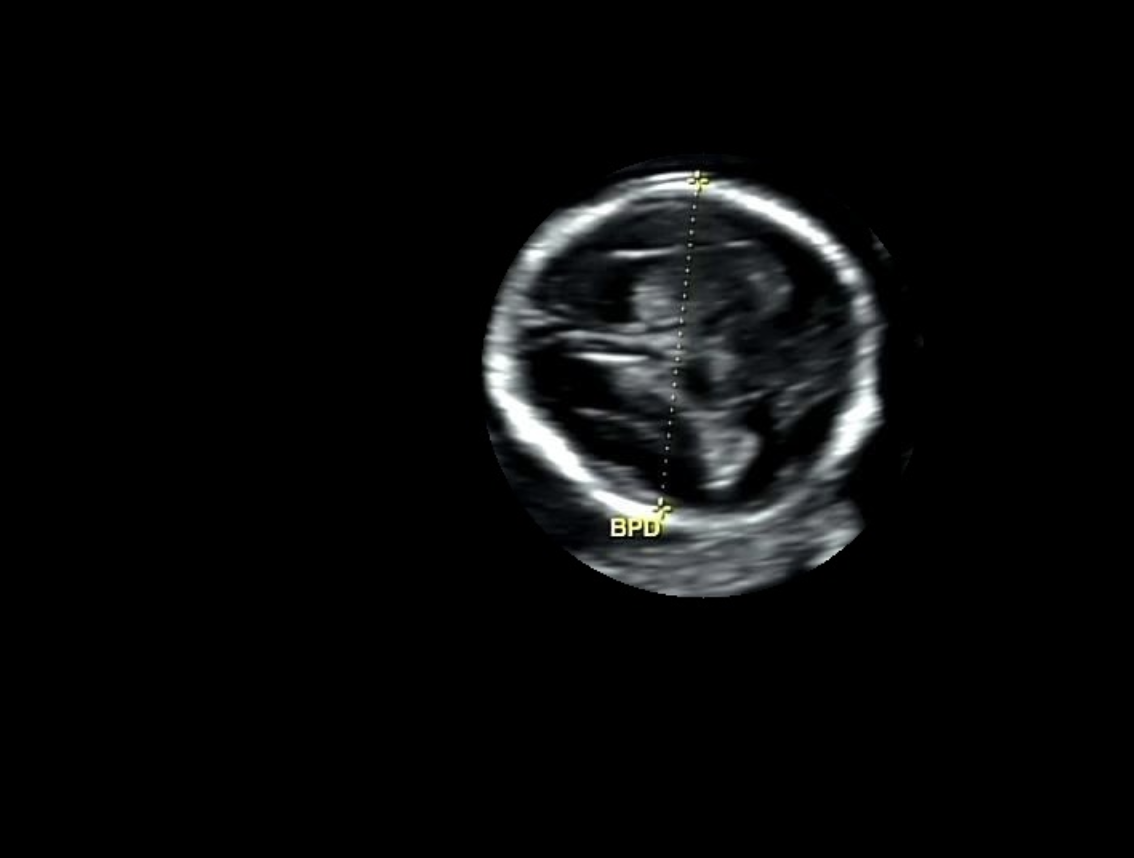

이미지 전처리 과정을 거쳐서 원하는 영역을 추출하도록 개선했다. 이미지 전 처리 과정이 잘 구축해두면 정확도가 높아진다. 이미지 전 처리 과정은 다음과 같다:

점선 원 찾기:

> 이미지에서 점선으로 이루어진 동그라미(원)을 검출한다.

> 원이 보이지 않으면 원의 크기를 키우거나 조건을 바꿔 여러 번 다시 시도한다.

원 주변 처리 (마스킹):

> 찾은 원을 기준으로 이미지를 잘라내고, 원 바깥부분은 지운다.